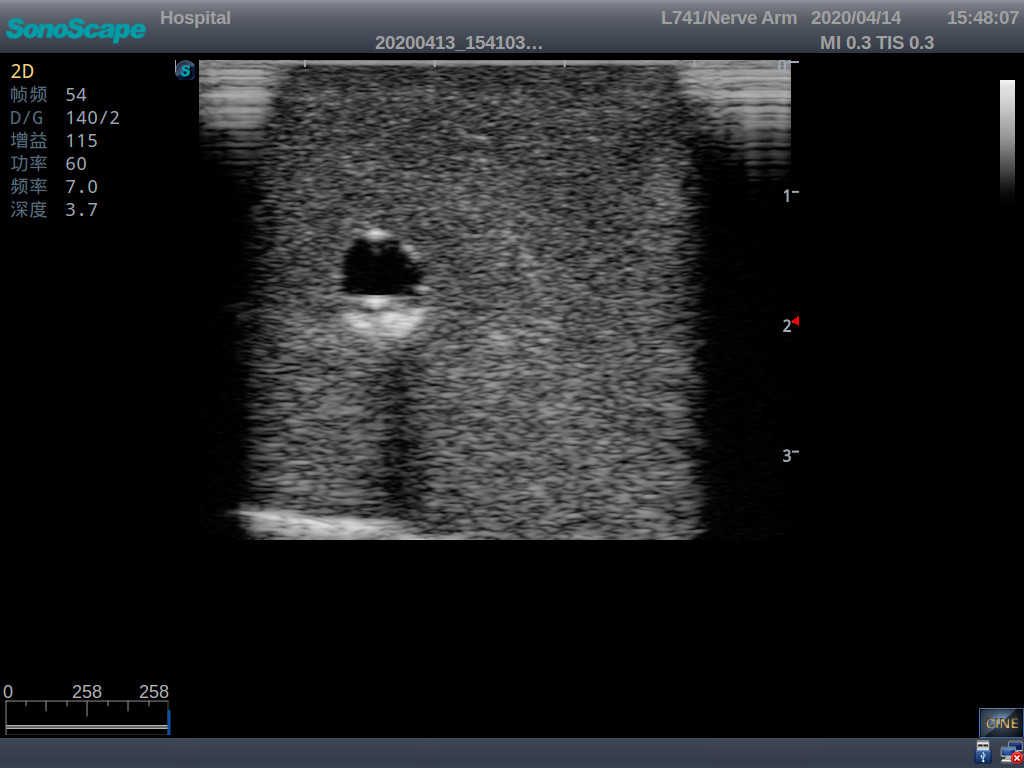

PICC Ultrasound Training Model

Model TYE1510.1

1)   Made of high molecular polymer ultrasound material, close to the real skin

2)   It can be used by real ultrasound machines

3)   Clear and real images of the tissues and organs (basilic vein and superior vena cava)

5)   Observe the guide wire marches

6)   Detect whether the catheter is properly placed